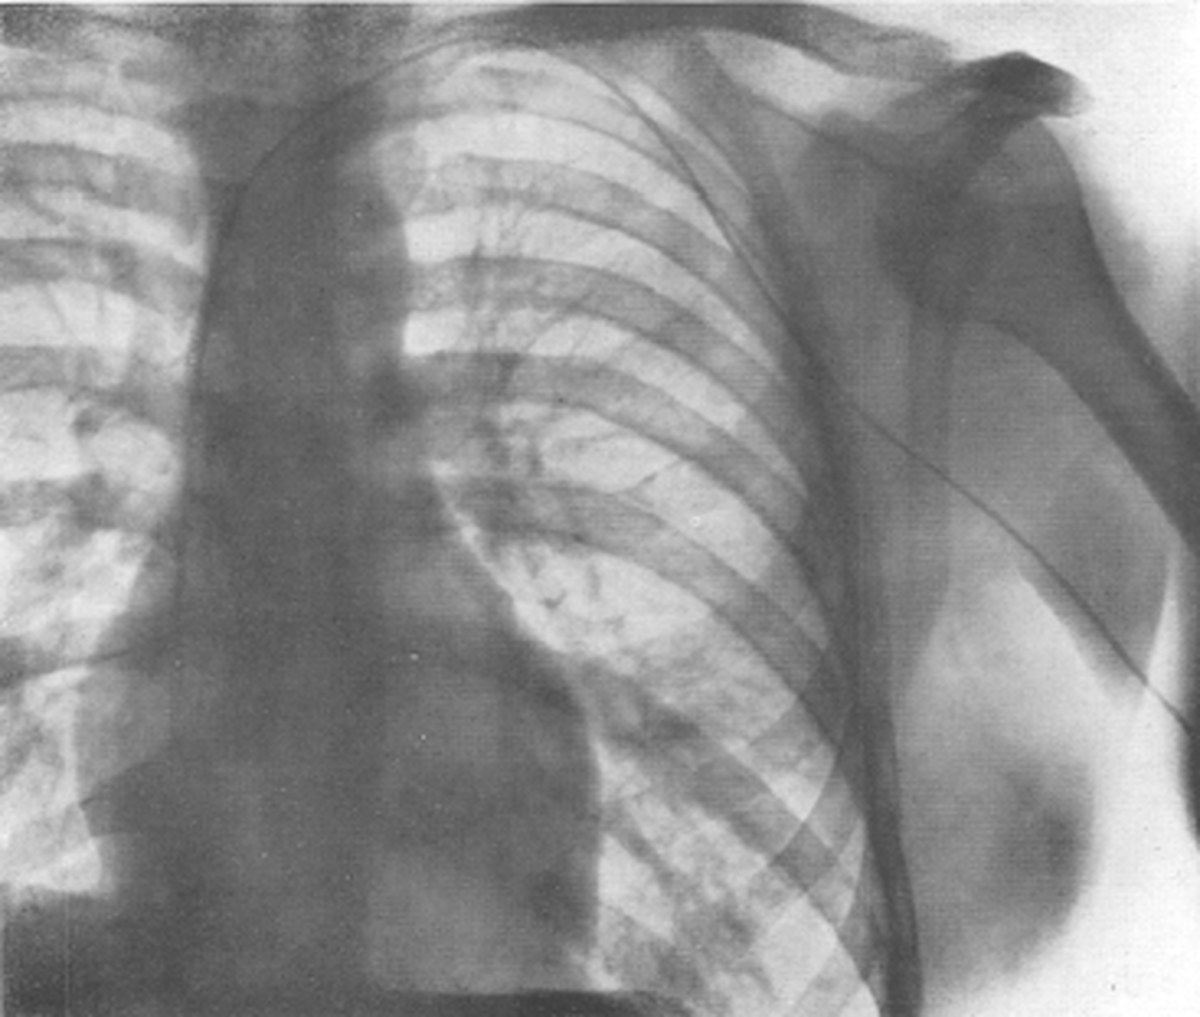

ورنر فورسمان در سال 1904 در برلين متولد شد و پس از تحصيل در رشته پزشكي دانشگاه برلين٬ در سال 1929 و زماني كه تنها يك پزشك جوان 25 ساله بود٬ يك كاتتر ابتدايي را از سياهرگ بازوي چپ خود٬ وارد بدن خود كرد و آنرا 65 ساتي متر جلو برد و سپس از بازو و قفسه سينه اش گرافي راديولوژي تهيه كرد و براي اولين بار در جهان نشان داد كه كاتتر داخل قلبش است !!

اما فورسمان با شهامت و شجاعت و با به خطر انداختن جان خود٬ اولين كاتتريزاسيون داخل قلبي را بر روي خودش انجام داد و در نوامبر سال 1929 مقاله آنرا به چاپ رساند. كار بينظير فورسمان كه انقلابي بزرگ در دانش پزشكي بود٬ پايه و اساس انجام آنژيوگرافي و كاتتريزاسيون داخل قلبي در سالهاي بعد بود.